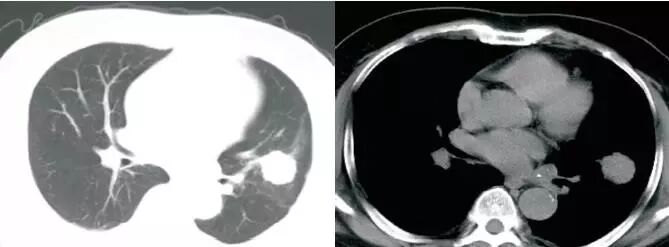

这是什么?

肿块,肺门增大,淋巴结肿大,并且,肿块和淋巴结互相融合,几乎是肺癌,大多数是小细胞肺癌。

小细胞肺癌为什么不做手术,不是绝对不做手术,而是小子跑得快,等你发现这个小鬼的时候,他已经到处转移了,晚期了。

小细胞肺癌,转移的最快

肿块包绕肺动脉干,肺动脉干变细,纵隔、肺门可见明显肿大淋巴结,相互融合,与肺门肿块分界不清,形成“冰冻纵隔”,这种贪得无厌的肿瘤,几乎都是小细胞肺癌。假如病理科报道:鳞癌。你可以要求病理科做免疫组化,再看看片子,不要冲动

纵隔、肺门可见明显肿大淋巴结,相互融合,与肺门肿块分界不清,形成“冰冻纵隔”,几乎都是可恶的小细胞肺癌。